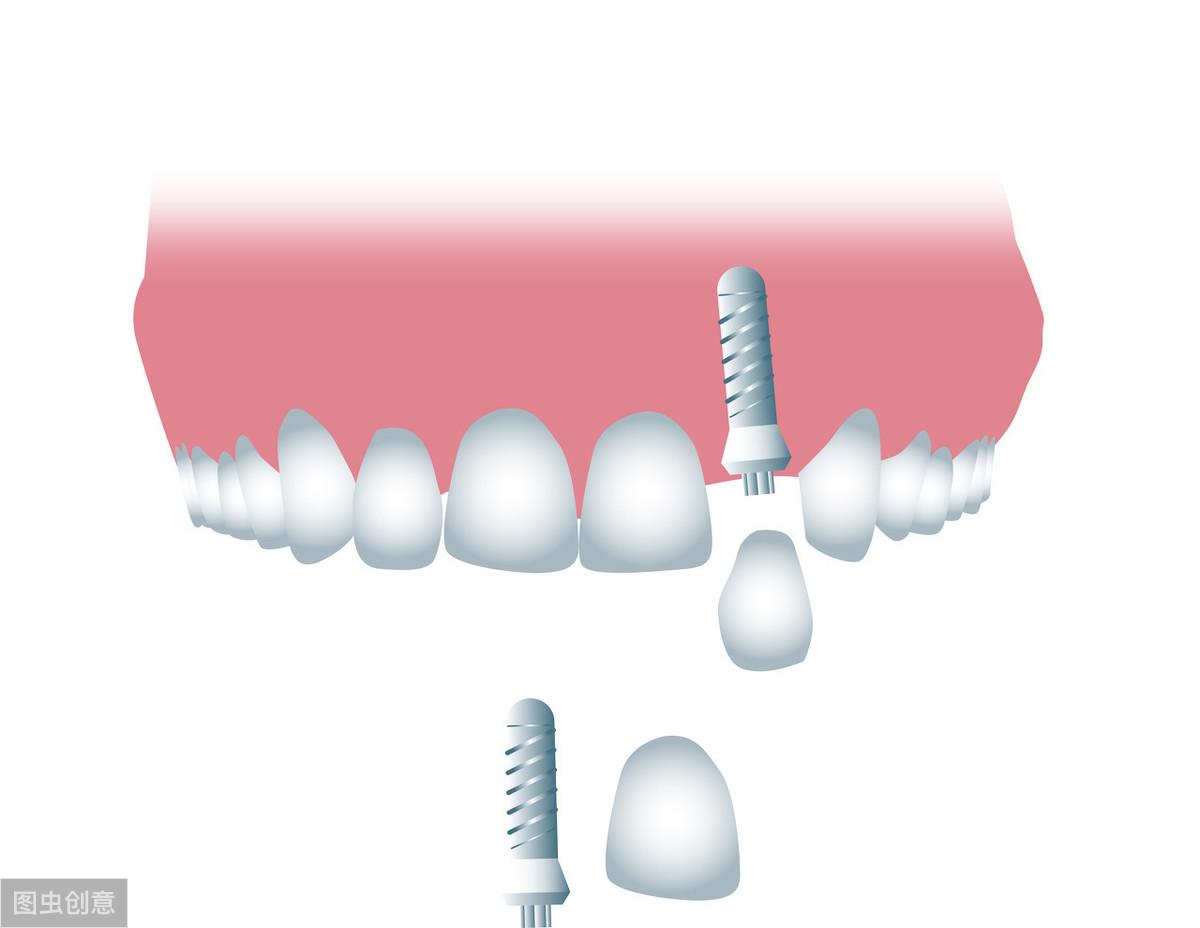

牙齒種植術(shù)是目前好的缺失牙齒修復(fù)技術(shù)之一,因?yàn)樗姆N植技術(shù)是通過手術(shù)將種植體植入到牙槽骨里,獲得了骨組織的固位支持,所以種植牙齒的穩(wěn)定性、性和使用年限都高,因此,種植牙從發(fā)展到現(xiàn)在也獲得了醫(yī)學(xué)界專家廣泛的認(rèn)可和大量有需要患者的喜愛。

二、種植牙適合什么年齡階段?因?yàn)榉N植牙齒需要把種植體植入到牙槽骨,所以需要骨骼維持在一個(gè)相對平穩(wěn)的狀態(tài),18歲左右人類的骨骼發(fā)育基本上就可以發(fā)育成熟,所以18歲以后就可以進(jìn)行牙齒種植了,種植年齡上限也沒有過高要求,即使是七八十歲的老人,只要身體健康符合標(biāo)準(zhǔn),也是可以進(jìn)行牙齒種植的;但是即便沒有年齡限制,種植牙也不是任何人都可以種,骨密度不符合種植標(biāo)準(zhǔn)、高血壓、心臟病、糖尿病和有出血性疾病的患者都不適合馬上進(jìn)行牙齒種植,如有植牙需求應(yīng)該等到病情穩(wěn)定或者采用其他替換方法。